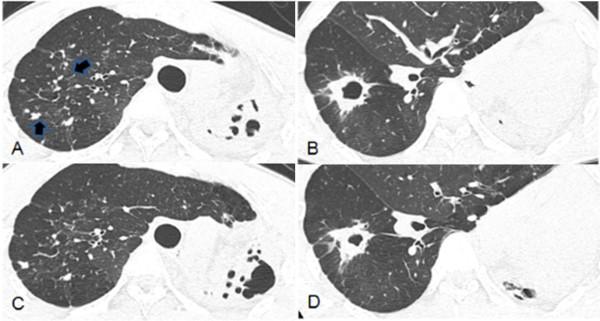

The purpose of the present study was to evaluate the changes in successive chest CT examinations in patients with pulmonary tuberculosis who achieved culture conversion with linezolid treatment. We reviewed the follow-up CT scans of 14 patients with pulmonary tuberculosis who had sputum-culture conversion after linezolid treatment. This study evaluated cavity, centrilobular nodules, consolidation, bronchial wall thickening, calcified nodule or consolidation, bronchiectasis, irregular lines, and lung destruction. The presence of pleural thickening, pleural effusion and lymphadenopathy was recorded. Follow-up CT scans showed a partial decrease in the extent of centrilobular nodules in all cases. Consolidation was partially cleared in 8 patients and newly developed consolidation was observed in 2 patients. All of the cavities showed a decrease in size and thickness. But the cavities persisted after linezolid treatment in 8 of 9 patients. Bronchial wall thickening was completely or partially cleared in 6 patients and 5 patients, respectively. Newly developed irregular lines, lung destruction and pleural thickening were observed in 1, 1, and 3 patients, respectively. Successive chest CT examinations in patients with linezolid treatment may help in the early assessment of linezolid treatment efficacy because of its rapid availability. Early assessment of linezolid treatment efficacy will help to set up a treatment plan, such as duration of treatment or linezolid dosage. However, they may not be useful for deciding pulmonary tuberculosis activity following linezolid treatment.

本研究的目的是评估接受利奈唑胺治疗且痰培养转阴的肺结核患者连续胸部CT检查的变化情况。我们回顾了14例接受利奈唑胺治疗后痰培养转阴的肺结核患者的随访CT扫描结果。本研究评估了空洞、小叶中心结节、实变、支气管壁增厚、钙化结节或实变、支气管扩张、不规则线影及肺毁损情况。记录胸膜增厚、胸腔积液及淋巴结肿大的情况。随访CT扫描显示,所有病例中小叶中心结节范围均有部分缩小。8例患者的实变部分吸收,2例患者出现新的实变。所有空洞的大小和厚度均减小。但9例患者中有8例在利奈唑胺治疗后空洞仍然存在。支气管壁增厚分别在6例和5例患者中完全或部分吸收。分别有1例、1例和3例患者出现新出现的不规则线影、肺毁损及胸膜增厚。由于利奈唑胺治疗的患者连续胸部CT检查结果可快速获得,因此有助于早期评估利奈唑胺的治疗效果。早期评估利奈唑胺的治疗效果将有助于制定治疗方案,如治疗持续时间或利奈唑胺剂量。然而,它们可能对判定利奈唑胺治疗后的肺结核活动情况并无帮助。